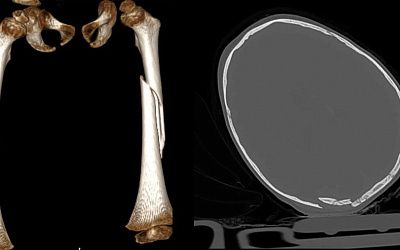

Улан-удэнец несколько дней мучился от застрявшей в пищеводе кости

Общество

18:33

2000